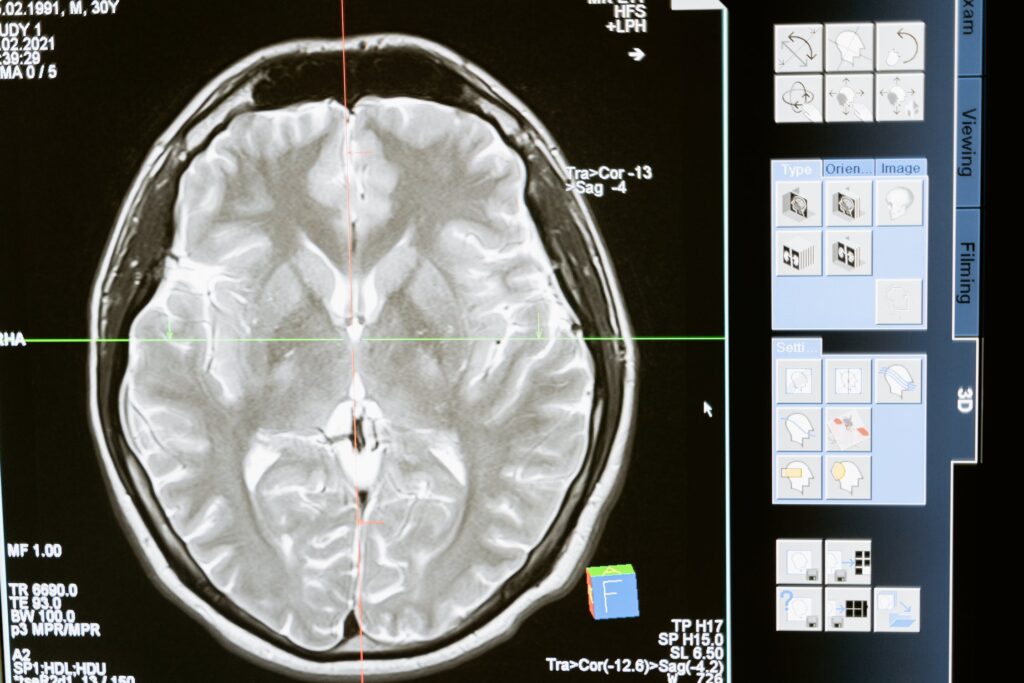

Imazheria funksionale e rezonancës magnetike, ose fMRI, është një mjet i përdorur nga neuroshkencëtarët për të fituar njohuri se si funksionon truri. Ndërsa një person kryen detyra të ndryshme mendore kur ndodhet në një skaner fMRI, skaneri gjeneron imazhe shumëngjyrëshe të trurit në veprim.

Ndërsa kjo teknologji ofron informacion se cilat zona të trurit janë duke u përdorur, ajo nuk zbulon se çfarë mendon, ndjen ose sheh personi. Vitet e fundit, studiuesit kanë përdorur inteligjencën artificiale (AI) për të interpretuar të dhënat fMRI, për të rindërtuar imazhet që një person sheh. Kjo teknologji mund të përdoret për të ndërtuar marrëdhënie të mundshme midis trurit dhe skanerit, për të ndihmuar njerëzit të cilët nuk mund të komunikojnë, siç janë individët që janë të pavetëdijshëm, por që kanë funksion neurologjik.

Në një studim të fundit, dy shkencëtarë nga Universiteti Osaka në Japoni, kombinuan të dhënat fMRI me një gjuhë të avancuar AI, që gjeneron imazhe për të përkthyer aktivitetin e trurit të pjesëmarrësve në fotografi. Ajo që u vu re, ishte fakti se fotografitë ngjanin në mënyrë të çuditshme me imazhet që njerëzit shihnin gjatë skanimeve. Imazhet origjinale dhe të rikrijuara mund të shihen në faqen e internetit të studiuesve. Studimi u pranua së fundmi për t’u prezantuar në Konferencën e 2023 mbi Vizionin Kompjuterik dhe Njohjen e Modeleve.

Skanimet e trurit, të përdorura në studimin e fundit, vijnë nga një bazë të dhënash kërkimore që përmban rezultatet e një studimi të mëparshëm, në të cilin tetë pjesëmarrës ranë dakord të shtriheshin rregullisht në një skaner fMRI dhe të shikonin 10,000 imazhe gjatë një viti. Rezultati përbëhet një databazë e madhe e të dhënave fMRI që tregon se si qendrat e shikimit të trurit të njeriut (ose të paktën truri i këtyre tetë pjesëmarrësve njerëzorë) reagojnë ndaj shikimit të secilit prej imazheve. Në studimin e fundit, studiuesit përdorën të dhëna nga katër prej pjesëmarrësve origjinalë.